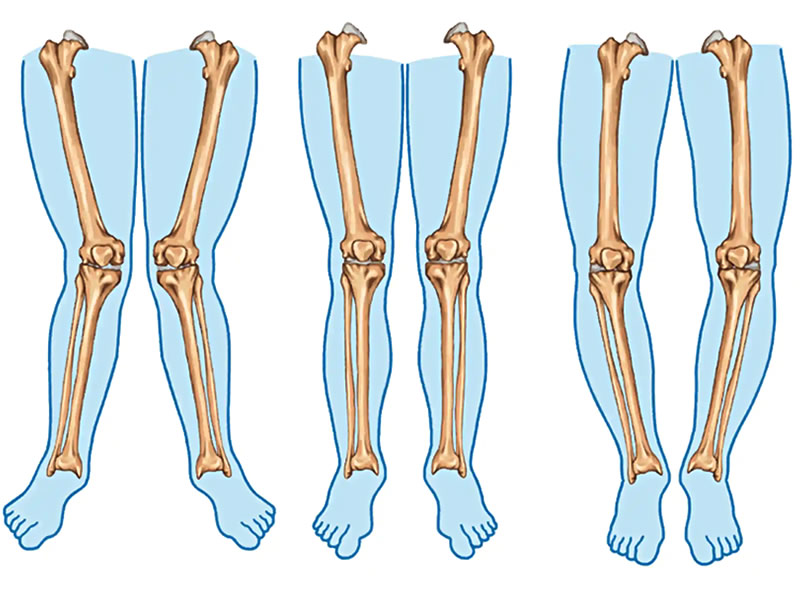

به گزارش بهداشت نیوز، برای اینکه وضعیت پاهای پرانتزی را درک کنید لازم است اول بدانید راستای «نرمال» پاها به چه معنی است. در وضعیت نرمال وقتی میایستید، باسنها و قوزکهای پا و زانوها همگی روی یک خط مستقیم قرار میگیرند. به عبارتی دیگر وقتی خطی از باسن به قوزک میکشید، این خط مستقیماً از مرکز زانو عبور میکند. اگر این خط در سمت داخل زانو قرار بگیرد؛ یعنی پاها پرانتزی هستند و اگر این خط از قسمت بیرون زانوها رد شود به آن پای ضربدری میگویند.

تعداد زیادی از بچههایی که میبینیم بهصورت فیزیولوژیکی پاهای پرانتزی دارند که کاملاً بیضرر بوده و نیازی به درمان ندارند. این پاهای پرانتزی بهتدریج و خودبهخود اصلاح میشوند و معمولاً تا سن ۵ سالگی کاملاً رفع خواهند شد. این بچهها اغلب پاهای پرانتزی خفیف و متقارن دارند.

تعداد زیادی از بچههایی که میبینیم بهصورت فیزیولوژیکی پاهای پرانتزی دارند که کاملاً بیضرر بوده و نیازی به درمان ندارند. این پاهای پرانتزی بهتدریج و خودبهخود اصلاح میشوند و معمولاً تا سن ۵ سالگی کاملاً رفع خواهند شد. این بچهها اغلب پاهای پرانتزی خفیف و متقارن دارند

پا پرانتزی در افراد بزرگسال خودبهخود و بهمرورزمان (مثل این عارضه در کودکان) برطرف نمیشود؛ بلکه تدریجاً بدتر شده و آرتروزی که وجود دارد باعث تشدید نا همراستا بودن پاها خواهد شد. پا پرانتزی در بزرگسالان یک ریسک فاکتور مستقل برای تحلیل مفصل زانو و زانودرد است. مطالعات گوناگونی نشان دادهاند اصلاح پا پرانتزی قبل از شروع مرحله آخر آرتروز میتواند نیاز به جایگزینی مفصل زانو را به تأخیر بیندازد یا کلاً از آن پیشگیری کند.

. فاصله گرفتن زانوها از هم